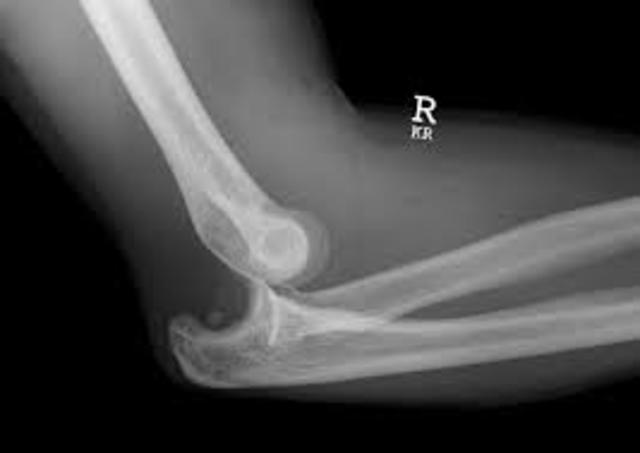

• dislocated elbow

dislocated elbow

read morei dislocated my elbow during a wrestling match, the first time this has happened